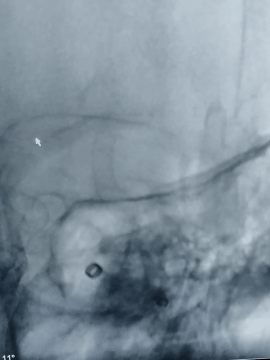

术后造影

术后正位即刻造影显示:Surpass Streamline血流导向密网支架整体贴壁良好,瘤腔内造影剂明显滞留。